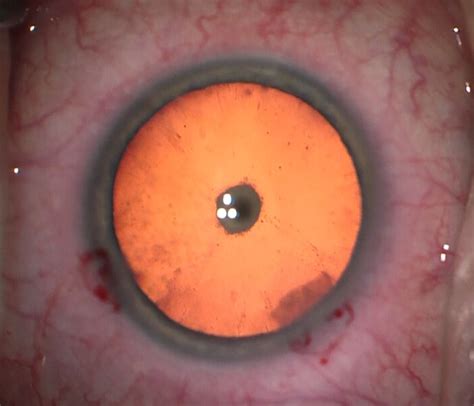

So, PSC stands for Posterior Subcapsular Cataract . Now, let’s dissect that a bit. A cataract, as you probably already know, is the clouding of the natural lens inside your eye. Think of your eye’s lens like the lens of a camera – it helps focus light onto the retina so you can see clearly. When a cataract develops, it’s like looking through a foggy window. But what makes a PSC different from other types of cataracts? The key is in the location. The term “posterior” means ‘at the back’, and “subcapsular” refers to the area just beneath the lens capsule (the membrane that surrounds the lens). So, a posterior subcapsular cataract is a specific type of cataract that forms on the back surface of the lens.

Why is location important? Because PSCs tend to have a more significant impact on vision compared to other types of cataracts, especially for near vision and in bright light. This is because of their location directly in the path of light as it enters the eye. Imagine a tiny imperfection right in the center of your camera lens – it’s going to mess up the image more than if it were on the edge. These cataracts are often smaller and develop more rapidly than other types, making early detection and management crucial. So, if you’re noticing glare, halos around lights, or difficulty reading, especially in bright conditions, a PSC might be the culprit. These symptoms arise because the clouding at the back of the lens scatters the light entering your eye, disrupting the sharp focus needed for clear vision. The glare and halos are particularly bothersome at night when your pupils dilate to let in more light, exacerbating the scattering effect. And near vision suffers because the posterior location interferes with the eye’s ability to focus up close. Therefore, understanding what PSC means and how it uniquely affects vision is a fundamental aspect of ophthalmology. It enables eye care professionals to accurately diagnose the condition and recommend the most appropriate treatment options, which we’ll explore later. Remember, the earlier a PSC is detected, the better the chances of managing its progression and restoring clear vision.

- Dilated Eye Exam: Eye drops are used to widen your pupils, allowing your doctor to get a better view of the entire lens, including the posterior capsule where PSCs form.

- Cataract Surgery: During cataract surgery, the cloudy lens is removed and replaced with a clear artificial lens called an intraocular lens (IOL). There are different techniques for cataract surgery, but the most common is phacoemulsification. In this procedure, the surgeon makes a small incision in the eye and uses ultrasound to break up the cataract, which is then gently suctioned out. The IOL is then inserted through the same incision. The great thing about cataract surgery is that it not only removes the cataract but also can correct other vision problems like nearsightedness, farsightedness, and astigmatism, depending on the type of IOL used.